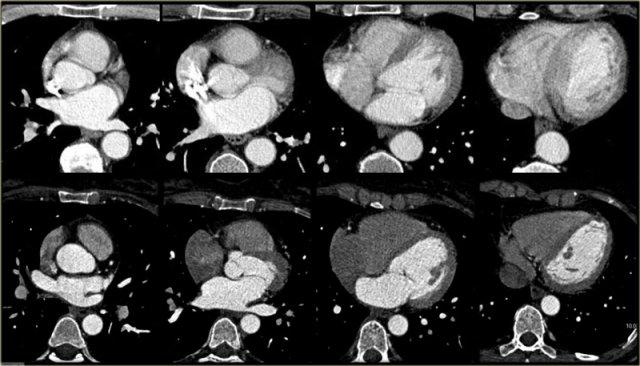

Các lát cắt ngang, như những lát cắt được hiển thị ở bên trái, hữu ích cho việc đánh giá tổng thể hình thái của tim và mối liên quan của nó với màng ngoài tim.